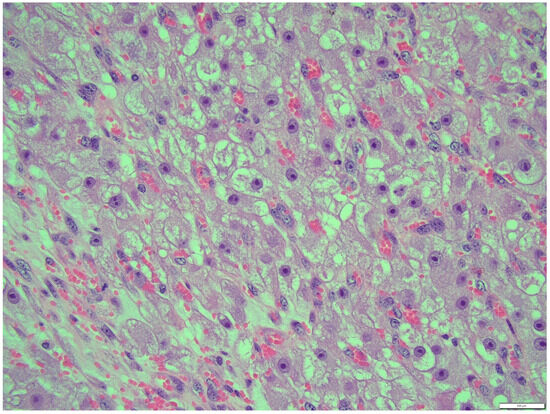

Thecoma cells had changed the nucleus/cytoplasm ratio in favor of cytoplasm (cytoplasm of thecoma cells was very abundant). The cytoplasm of thecoma cells was irregular in shape and amount, with distinct borders and different sizes and amounts of vacuoles. Nuclei were large, with moderate size and shape variation and large, irregular size nucleoli (macronucleoli) (Figure 12). The mitotic rate was moderate in thecoma tissues—10 normal mitoses per 10 fields at 400 magnification (Figure 13).

Figure 8. Thecoma: population of cells showing ovoid to round nuclei and pale gray abundant oval, round cytoplasm. The distinct large nucleolus inside the nucleus is present (blue arrow). HE, 200× magnification. Black arrow—part of fibroma.

Figure 12. Nucleus were large, with moderate size and shape variation, with large, irregular size nucleolus (macronucleoli), thecoma part. HE, 400× magnification.

Figure 13. Mitotic rate was moderate in thecoma tissues—10 normal mitoses per 10 fields at 400× magnification (thecoma part), HE.